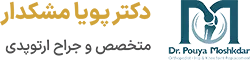

پزشک برای تشخیص شکستگی ناحیه لگن در وهله اول معاینات فیزیکی را انجام میدهد و سپس جهت اطمینان کامل از روشهای مختلف تصویربرداری استفاده میکند. تصویربرداری اشعه ایکس یکی از روش های تشخیص شکستگی است. با انجام این نوع تصویربرداری تصاویر دقیقی از استخوان ها به دست میآید و پزشک میتواند محل دقیق شکستگی را تشخیص دهد.

MRI یکی دیگر از روش های تصویربرداری است که با استفاده از یک آهنربا پرقدرت تصاویری دقیق از بافت ها، عضلات و استخوان ها به دست خواهد آمد. سومین روش تشخیص شکستگی سی تی اسکن است. با استفاده از سی تی اسکن نیز پزشک میتواند تصاویر دقیقی را از ناحیه لگن و استخوان های آن مشاهده کند.